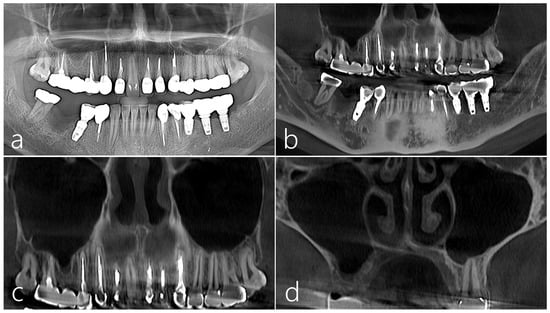

2.1. Case 1

2.2. Case 2

2.3. Case 3

2.4. Case 4